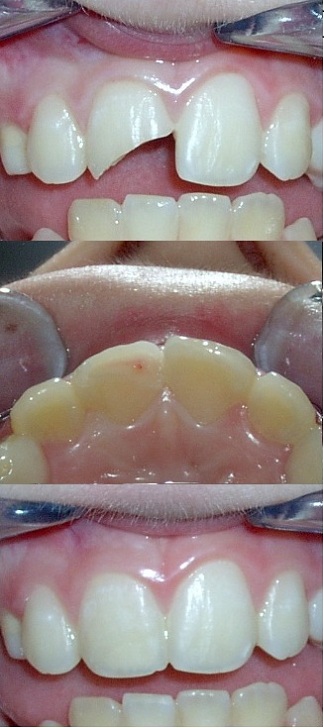

TRAUMI DENTALI

Non è così infrequente che un bimbo, in seguito ad un trauma durante le sue normali attività, si provochi la frattura di un dente. La gravità del danno dipende sostanzialmente dall'età del bambino: se è in età prescolare i denti solitamente interessati sono quelli decidui ed il problema conseguente è per definizione solo temporaneo; raramente gli elementi definitivi sottostanti riportano un danno e ciò avviene solo in caso di forti traumi intrusivi in cui l'elemento deciduo viene spinto dentro l'osso.

Di natura diversa è la gestione delle fratture dentali in età scolare, infatti, dopo i 6 anni, normalmente erompono gli elementi definitivi ed un danno a questi elementi è sempre permanente.

Gli elementi più frequentemente interessati sono gli incisivi superiori, in particolar modo gli incisivi centrali.

Dopo un trauma che porta alla frattura di un elemento dentale occorre:

L'odontoiatra, dopo aver valutato il danno, escluso eventuali fratture, controllato la mobilità e la vitalità degli elementi interessati, provvederà alla pianificazione degli interventi necessari.

Se ci si trova in presenza di esposizione della polpa, come si può vedere nella foto a lato, quest'ultima potrebbe aver subito un danno e potrebbe rendersi necessaria la sua rimozione; se gli elementi traumatizzati presentano mobilità in seguito a microfratture della corticale ossea in cui sono inseriti può rendersi necessario immobilizzarli per un periodo legandoli agli elementi adiacenti.

Frequentemente possono essere presenti concomitanti lesioni lacerocontuse al labbro, in tal caso l'odontoiatra valuterà l'eventualità di posizionare qualche punto di sutura.

Se non è stato possibile rinvenire i frammenti fratturati, la ricostruzione può avvenire in due modi, direttamente in bocca al paziente oppure rilevando un'impronta, facendo eseguire la ricostruzione delle parti mancanti ad un bravo odontotecnico e provvedendo successivamente alla loro cementazione.

Senza dubbio la situazione più favorevole è quella in cui si hanno a disposizione i frammenti originali, in tal caso è possibile, con buona padronanza della tecnica, reincollarli, limitando al massimo le discrepanze di forma e colore, con un risultato molto stabile nel tempo.

Qualora ciò fosse possibile, è sempre di primaria importanza intervenire tempestivamente per risolvere quanto prima il trauma psicologico della perdita dell'integrità dell'immagine di sè. Il piccolo paziente arriva in studio sempre molto preoccupato per il danno permanente che si è creato e riuscire a "cancellarlo" rapidamente, e in modo valido dal punto di vista estetico, crea un immediato giovamento che si riflette positivamente sulla sua salute psicologica e di tutto il nucleo familiare.